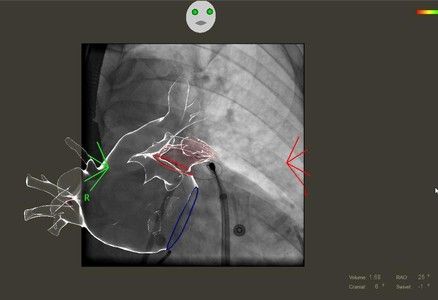

L’ablazione transcatetere è un intervento eseguito attraverso l’inguine del paziente (passando dalle vene femorali), che permette di applicare energia (radiofrequenza) per bruciare la porzione di cuore (atrio sinistro) dalla quale la aritmia si genera. Non sempre però l’ablazione abolisce efficacemente l’aritmia, in particolare in pazienti con cuore “affaticato” (dilatazione dell’atrio sinistro) o con aritmie di lunga data. Prevedere la probabilità di successo dell’intervento consentirebbe di eseguire la procedura nei candidati con ottima probabilità di successo ed evitare invece l’intervento in quelli in cui la previsione di successo sia bassa.